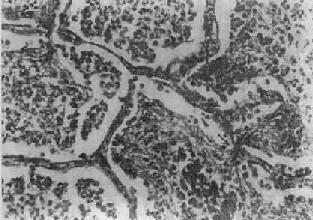

图9-15 大叶性肺炎 肺泡腔内充满纤维素性渗出物,纤维素丝穿过肺泡间孔,使相邻肺泡内的纤维素网互相连接

二、肺炎肺炎(pneumonia)通常是指肺的急性渗出性炎症,为呼吸系统的多发病、常见病。据世界卫生组织调查,肺炎死亡率占呼吸系统急性感染死亡率的75%。在我国,各种致死病因中,肺炎占第5位。肺炎可由不同的致病因子引起,根据病因可将肺炎分为感染性(如细菌性、病毒性、支原体性、真菌性和寄生虫性)肺炎,理化性(如放谢性、吸入性的类脂性)肺炎以及变态反应性(如过敏性和风湿性)肺炎。由于致病因子和机体反应性的不同,炎症发生的部位、累及范围和病变性质也往往不同。炎症发生于肺泡内者称肺泡性肺炎(大多数肺炎为肺泡性),累及肺间质者称间质性肺炎。病变范围以肺小叶为单位者称小叶性肺炎,累及肺段者称节段性肺炎,波及整个或多个大叶者称大叶性肺炎。按病变性质可分为浆液性、纤维素性、化脓性、出血性、干酪性、肉芽肿性或机化性肺炎等不同类型。 (一)细菌性肺炎 1.大叶性肺炎 大叶性肺炎(lobar pneumonia)主要是由肺炎链球菌感染引起,病变起始于肺泡,并迅速扩展至整个或多个大叶的肺的纤维素性炎。多见于青壮年,临床表现为骤然起病、寒战高烧、胸痛、咳嗽、吐铁锈色痰、呼吸困难,并有肺实变体征及白细胞增高等。大约经5~10天,体温下降,症状消退。 【病因和发病机制】 95%以上的大叶性肺炎由肺炎链球菌引起,尤以Ⅲ型者毒力最强。此外,肺炎杆菌、金黄色葡萄球菌、溶血性链球菌、流感嗜血杆菌也可引起。受寒、疲劳、醉酒、感冒、麻醉、糖尿病、肝、肾疾病等均可为肺炎的诱因。此时,呼吸道的防御功能被削弱,机体抵抗力降低,易发生细菌感染。细菌侵入肺泡后在其中繁殖,特别是形成的浆液性渗出物又有利于细菌繁殖,并使细菌通过肺泡间孔或呼吸细支气管迅速向邻近肺组织蔓延,从而波及整个大叶,在大叶之间的蔓延则系带菌渗出液经叶支气管播散所致。 【病理变化】 病变一般发生在单侧肺,多见于左肺下叶,也可同时或先后发生于两个以上肺叶。病变基本特征是肺的微循环障碍。由于毛细血管通透性增高,大量纤维蛋白原渗出于肺泡,使肺组织大面积广泛实变。病变早期,肺叶充血、水肿,肺泡腔内有大量浆液性渗出物,混有少数红细胞、中性粒细胞和巨噬细胞,并含有大量细菌。1~2天后,即有大量纤维蛋白原渗出,肺泡腔内充满混有红细胞、中性粒细胞、巨噬细胞的纤维素性渗出物,纤维素丝可穿过肺泡间孔与相邻肺泡中的纤维素网相连(图9-15)。病变肺叶质实如肝,明显肿胀,重量增加,呈灰白色(图9-16)。如血管损伤较重、出血较多,外观可呈红色。大约经5~10天,炎症消退,细菌被吞噬细胞吞噬清除,渗出物被溶解,或经淋巴管吸收或被咳出。大叶性肺炎时,肺组织常无坏死,肺泡壁结构也未遭破坏,愈复后,肺组织可完全恢复其正常结构和功能。